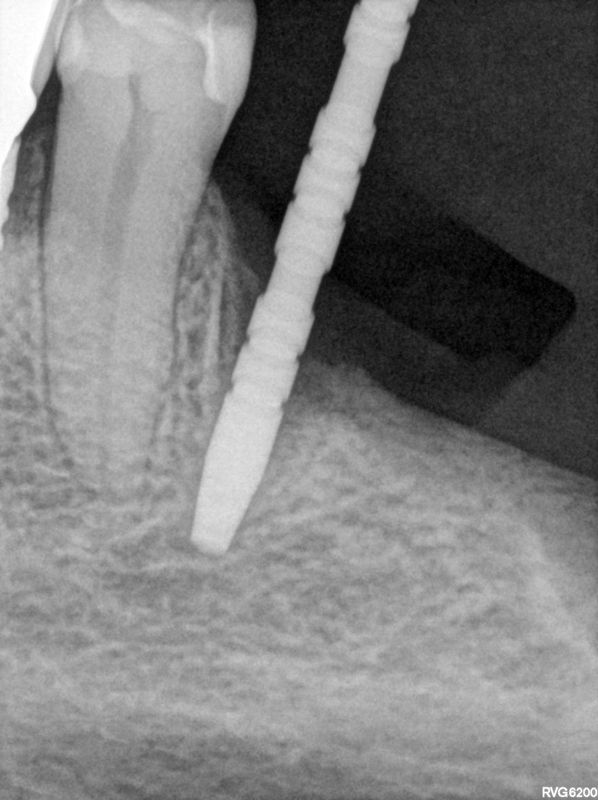

fredlibc | all galleries >> Galleries >> JGolos - llq implants > R9.jpg

R9.jpg